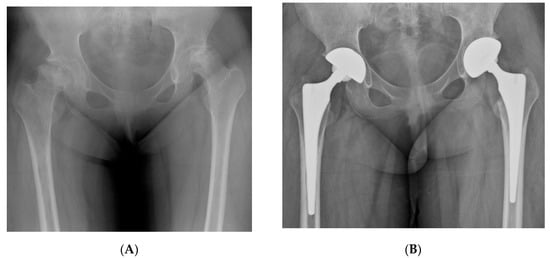

Figure 2.

(A,B) Preoperative and postoperative hip radiographs of a 33-year-old woman with cognitive dysfunction and visual disturbance after removal of recurrent craniopharyngioma. She underwent simultaneous bilateral THA due to ONFH. (C,D) Radiographs of the same woman on the 15th postoperative day, when she visited the emergency department due to severe pain in the left hip. Anteroposterior and lateral images demonstrated anterior hip dislocation. (E) Hip radiograph after performing closed reduction followed by abduction brace application under general anesthesia. (F) Eight-year postoperative radiograph showed stable implant fixations.